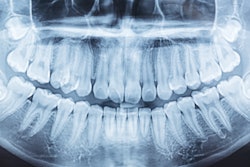

Patent No. 11,553,874 covers dental image feature detection powered by machine learning. The technology aims to help dentists detect dental diseases on x-rays and match those findings to patient records.